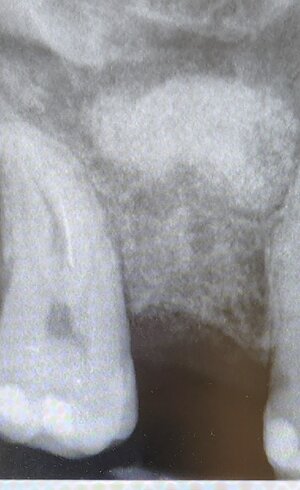

Implantologia Guidata: chirurgia mini-invasiva di alta precisione.